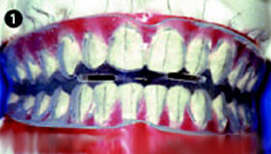

Elasto-Bond

Чтобы сделать возможным «прямое» приложение силы в вертикальном, небном или лингвальном направлениях, перед изготовлением прибора на зубах фиксируют несъемные элементы. Из эстетических соображений можно использовать мало бросающиеся в глаза пластмассовые кнопки или брекеты цвета зубов (рис.3).

Название “Bond” указывает на наличие дополнительного крепления – приклеенных деталей на зубах. В данном случае использованы специальные брекеты Elasto , их наличие обеспечивает передачу сил, возникающих в Elasto-Bond в вертикальном направлении (рис.1). Этот метод представляет собой комбинацию несъемных и съемных лечебных конструкций. Elasto-Bond также изготавливается из высокоэластичного Silasto 50.

Если вертикальная щель в переднем отделе превышает два миллиметра, в аппарате делают горизонтальный разрез, чтобы возникающая растягивающая сила оставалась биологически приемлемой. Сила возврата в исходное положение разделенного на части аппарата Elasto-Bond достаточна для того, чтобы способствовать зубоальвеолярному удлинению зубов, так как необходимо усилие примерно 25 грамм/сил. В Set-up зубы перемещают так, чтобы полностью устранить вертикальную щель, даже при выраженной аномалии достаточно одного аппарата.

Для данного типа аномалий метод Elasto-Bond является настоящей альтернативой лечению с помощью несъемных аппаратов. Elasto-Bond можно использовать как в начале лечения так и на любом другом этапе. С эстетической точки зрения использование прозрачных брекетов также является преимуществом. При этом методе лечения брекеты эластопозиционер приклеиваются на зубы до снятия слепков. В большинстве случаев нет необходимости в приклейке брекетов на оба зубных ряда полностью, достаточно только передней группы зубов (резцов и клыков).для приклейки брекетов Elasto можно использовать прямой и непрямой метод. Чтобы достичь в аппарате точной передачи пазов, гипсовые модели гравируют, полностью удаляя «брекеты», и заменяют их оригинальными брекетами, которые могут использоваться повторно.